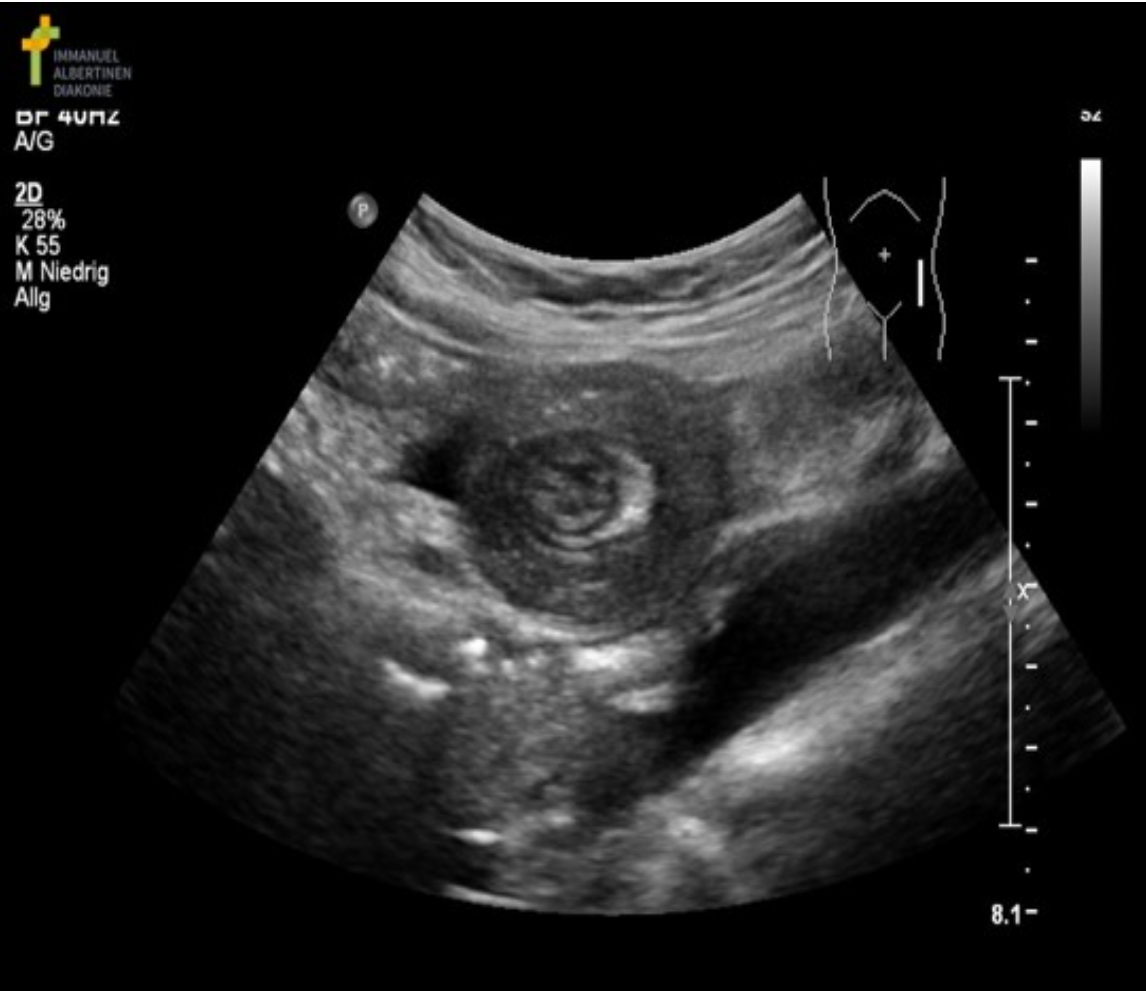

A 3yr old is scanned due to vomiting and a palpable lump in the abdomen.

These findings are most suggestive of:

C. Intussusception

The image demonstrates intussusception with the the inversion of one portion of the intestine within another. Note the body marker indicates the area of interest is on in the mid to lower quadrant on the left side. The aorta is also visualized on the image. Pyloric stenosis is diagnosed in early infancy and would be located in the epigastric/RUQ area. The aorta would not be demonstrated in the area of the appendix.